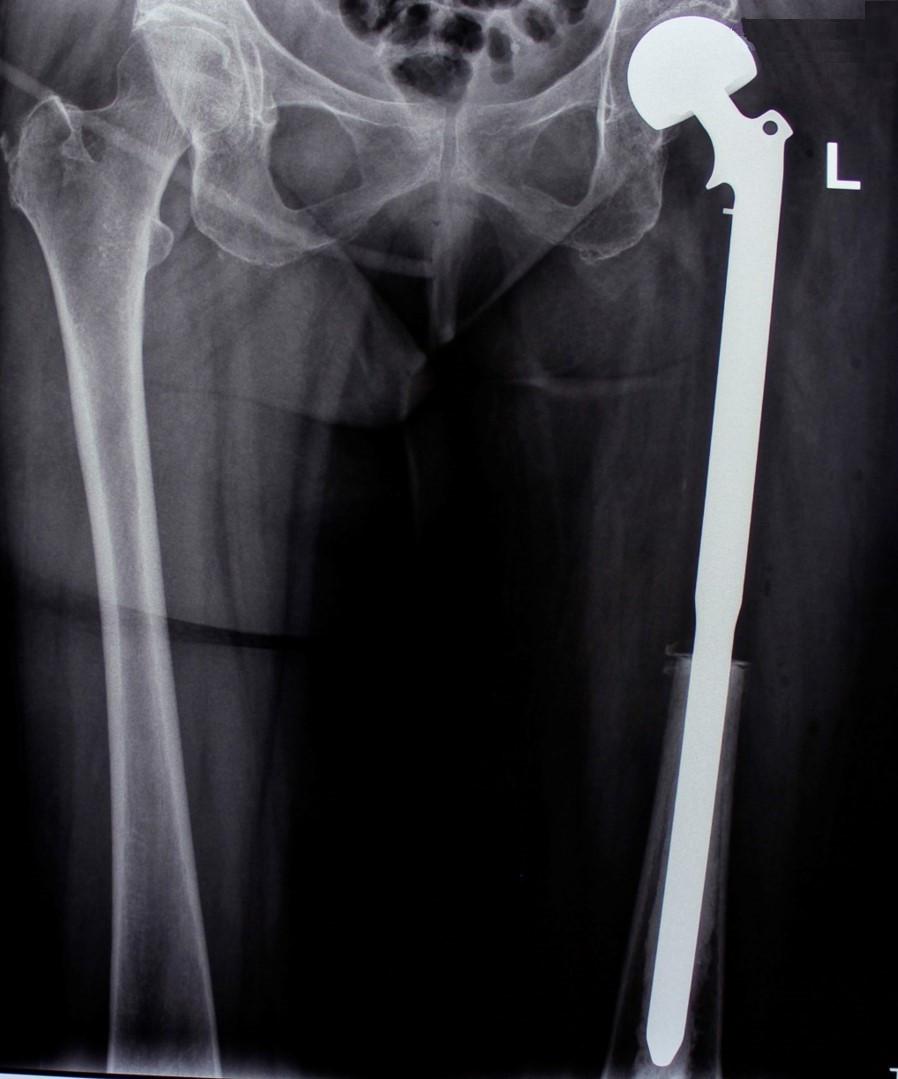

2. Բժշկական տարբեր կենտրոններում հետազոտվելուց հետո՝ 17-ամյա պատանին դիմել է «Նաիրի» ԲԿ։ Համապատասխան հետազոտություններ անցնելուց հետո՝ բուժառուի մոտ հայտնաբերվել է ոլոքի օստեոսարկոմա (ոսկրային քաղցկեղ): Նախավիրահատական բուժում ՝ քիմիոթերապիա, ստանալուց հետո՝ «Նաիրի» ԲԿ ում կատարվել է օրգանապահպան վիրահատություն : Հեռացվել են ծնկահոդն ու ոլոքի վերին երորդականը: Առաջացած դեֆորմացիան շտկել է Եվրոպայից պատվիրված էդոպրոթեզով, որը հնարավորություն է տվել պահպանել վերջույթի գործառույթը՝ քայլել, վազել և այլն։ Հետվիրահատական շրջանում բուժառուն ստացել է քիմիոթերապիա։ Այժմ գտնվում է բժիշկների հսկողության ներքո։

Վիրահատությունից առաջ

Վիրահատությունից հետո